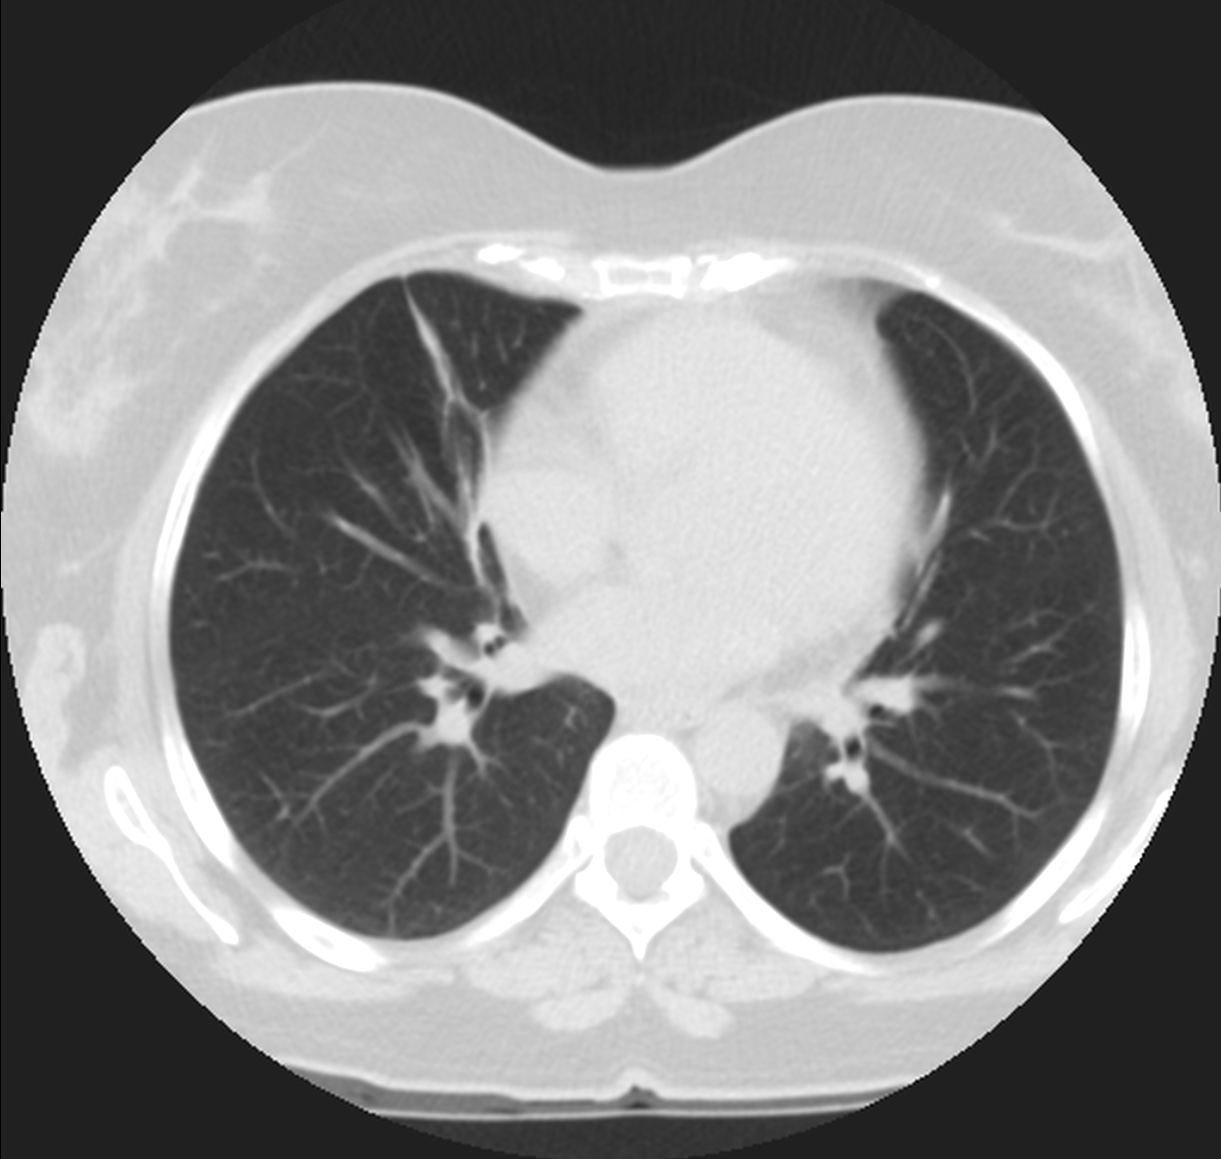

CASO: cáncer de mama. Control anual.

Hallazgos:

- Se observa un aumento de densidad con agrupación broncovascular que produce un borramiento del borde cardicaco derecho; hallazogos compatibles con atelectasia en el lóbulo medio. Véase el TC a continuación: